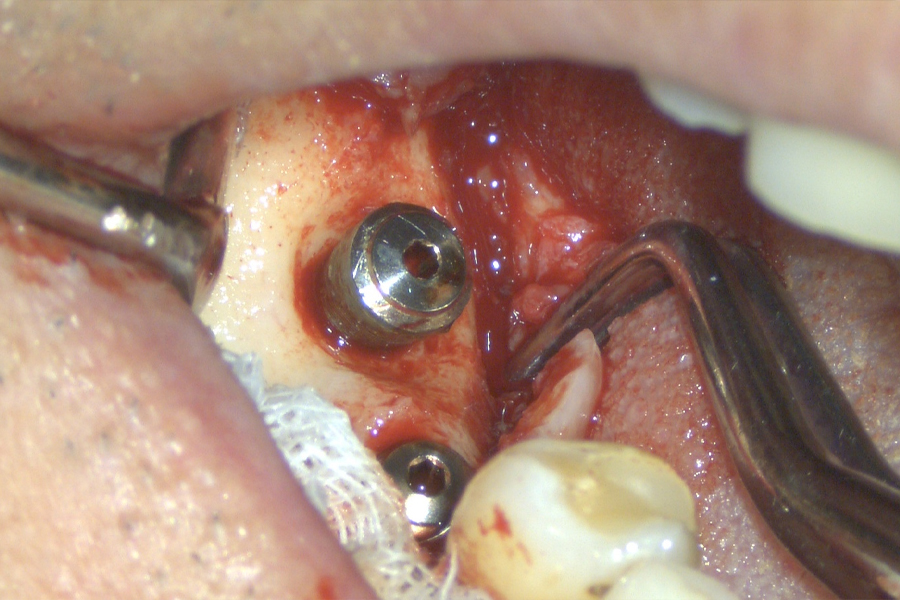

こちらの患者様は2002/02/21、16年前に当医院で私がインプラント手術致しました。

16年後の定期健診でインプラント周囲炎を起こしていることを発見致しました。

レントゲン上で左のインプラント周囲の骨が吸収しているのが観察されます。(2018年2月撮影)

インプラントは骨と結合(oseoinyerration)しやすいように表面の構造が塑像になっていてそのことが一旦、プラークで汚染されるとインプラント体を清掃して無菌的にしてインプラント周囲炎を治癒させる方法がありませんでした。

Er:Yagレーザーによりこの塑像な構造を洗浄して歯石・細菌性プラークを綺麗に除去することが出来るようになりました。

手術時と術後4ヶ月の写真です。

4ヶ月前のオペ時のビデオです。